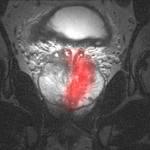

PMI's device uses an MRI for imaging and a proprietary planar ultrasound applicator for treatment. The MRI precisely guides the probe that heats the cancerous tissue to effectively destroy the diseased area. In the past, the magnetic nature of electric motors and their metal components made it impossible for motorized medical devices to function within the MRI environment. To overcome this challenge, PMI selected Nanomotion's HR2-1-N-3 piezo ultrasonic non-magnetic motors to rotate the device's probe. When combined with the real-time non-invasive visibility into the human body provided by the MRI, the sophisticated low-speed Nanomotion actuators in PMI's device enable medical professionals to operate the probe at a microscopic scale to conduct this groundbreaking procedure.